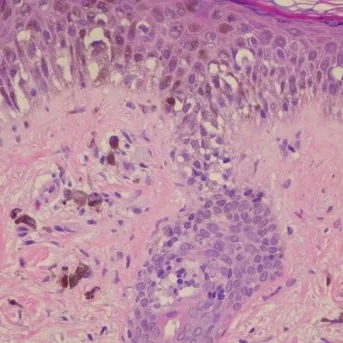

St. Joseph Dermatopathology, founded in 1990, is an independent lab dedicated to the science of Dermatopathology. We provide microscopic evaluation and diagnosis of skin, hair and nail tissue exclusively. Our goal is to provide the best service possible, the service that you expect.

- Pathological tissue exam (biopsy)